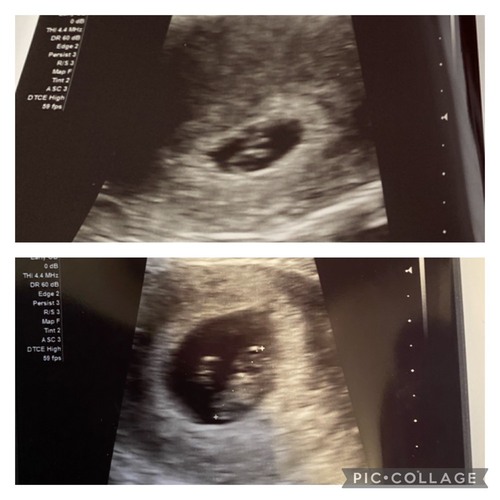

Wat denken jullie? 6+3 uitwendige echo, kwam er zelf niet helemaal uit, bij mijn dochter klopte het wel en de nub ook. Ben heel benieuwd nu 🥰

Het dooier zakje leek rechts te zitten toen ze inzoomde